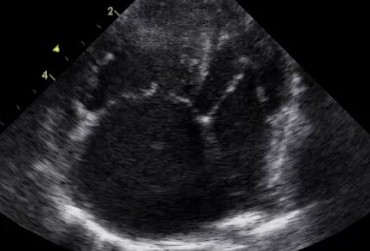

Zwężenie zastawki trójdzielnej jest jedną z form dysplazji pojawiającą się w różnym stopniu nasilenia (najczęściej łącznie z niedomykalnością zastawki) zarówno u psów, jak i u kotów. Cechami charakterystycznymi definiującymi zwężenie zastawki trójdzielnej są: obecność rozkurczowego wybrzuszenia (doming) płatków zastawki, zmniejszona ruchomość płatków, zmniejszona średnica ujścia zastawki. Mimo że zmiany morfologiczne aparatu trójdzielnego są typowe w przebiegu TVD i są znakiem rozpoznawczym tej choroby, nie są one zawsze bardzo silnie wyrażone i nie zawsze można mieć bezsprzeczną pewność diagnostyczną, bazując na badaniu echokardiograficznym [10]. Przypadki takie zdarzają się przede wszystkim u pacjentów, u których nie postawiono diagnozy we wczesnym etapie życia, a którzy pojawiają się na badaniu dopiero w starszym wieku z zaawansowanymi zmianami i niejednokrotnie z klinicznymi objawami prawostronnej niewydolności mięśnia sercowego i towarzyszącymi zaburzeniami w rytmie. W takich przypadkach obraz choroby może przypominać arytmogenną kardiomiopatię prawokomorową (arrhythmogenic right ventricular cardiomyopathy – ARVC) [1, 8]. Preekscytacja jest często obserwowana u ludzi z anomalią Ebsteina. U zwierzat, podobnie jak u ludzi, obecność dodatkowej drogi przewodzenia może nigdy nie prowadzić do rozwoju tachykardii nadkomorowej lub arytmia ta pojawiać się może dopiero w późniejszym okresie życia. Opisany przypadek jest przykładem pacjenta z dysplazją zastawki trójdzielnej i prawostronną niewydolnością serca będącą najprawdopodobniej konsekwencją tachykardii nadkomorowej.